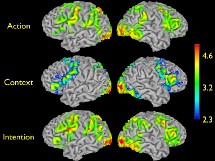

Iacoboni/Ahmanson-Lovelace Brain Mapping Center at UCLA

Para el experimento fueron analizados 33 sujetos con un sistema funcional MRI, que genera imágenes de resonancia magnética del cerebro. Se trata de una de las tecnologías más avanzadas para examinar la estructura, tejidos y fluidos internos del cuerpo humano, capaz de producir imágenes nítidas en dos o tres dimensiones. Estas imágenes se realizan utilizando un poderoso imán y ondas radiales.

Estos 33 voluntarios visualizaron alternativamente tres tipos de estímulos en vídeos cortos: primero una mano que agarraba una taza sin que este movimiento se encontrara enmarcado en un contexto; después sólo el contexto: un servicio de té completo con la comida y la bebida servidas; y finalmente los movimientos de beber o de limpiar dentro del contexto reflejado.

Se descubrió que las acciones realizadas dentro de contexto, en comparación con las realizadas fuera de él, aumentan el flujo de la sangre en la parte posterior del gyrus frontal inferior del cerebro, conocido por su importancia en la ejecución del control, y también en los sectores adyacentes del la corteza ventral premotora, donde las acciones de las manos se representan. El incremento del fluido sanguíneo es siempre un indicador de la actividad neuronal.

Este hecho implica que las neuronas espejo se activan en mayor grado cuando las acciones motoras que vemos no son aisladas, sino que se encuadran en un entorno que para nosotros tiene un significado determinado, lo que implica cierta capacidad de interpretación neuronal de identificación de las intenciones de la persona que tenemos enfrente.